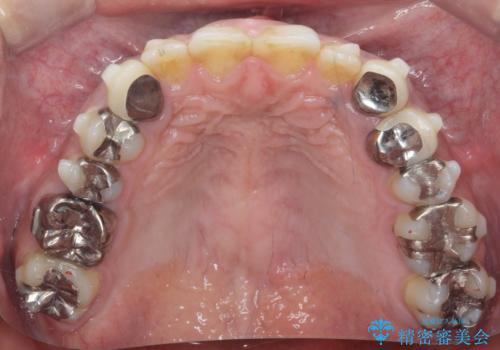

- 治療計画

- 長年虫歯の治療を受け続けたことで銀歯・コンポジットレジン修復だらけになってしまい、今後の見た目や歯を大切にするためにセラミック治療矯正治療を希望され来院されました。

マイクロスコープを用いた精密根管治療やセラミック治療、マウスピース矯正治療を一つの医院で行うことのできる当法人ならではの総合歯科治療を実践していきます。